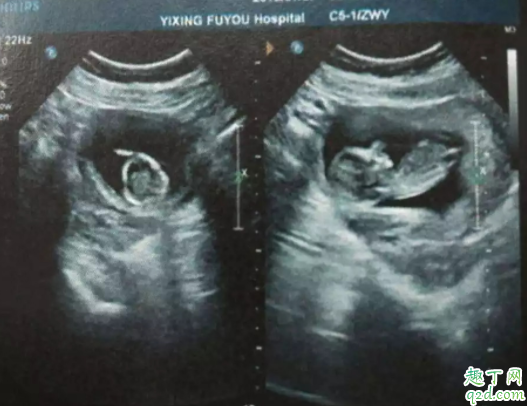

所以若有孕婦發(fā)生先兆流產(chǎn)跡象,建議到醫(yī)院做子宮和輸卵管的全面檢查(檢測(cè)孕酮值和hcg值),逐一排查原因。

如果孕酮值較低,但無(wú)陰道出血和腹痛癥狀,彩色多普勒超聲顯示胎兒正常,則無(wú)需擔(dān)心,心理壓力也是導(dǎo)致流產(chǎn)的因素之一。早期流產(chǎn)最常見(jiàn)原因是胚胎或胎兒染色體異常,只有少數(shù)患者因激素缺乏所致。